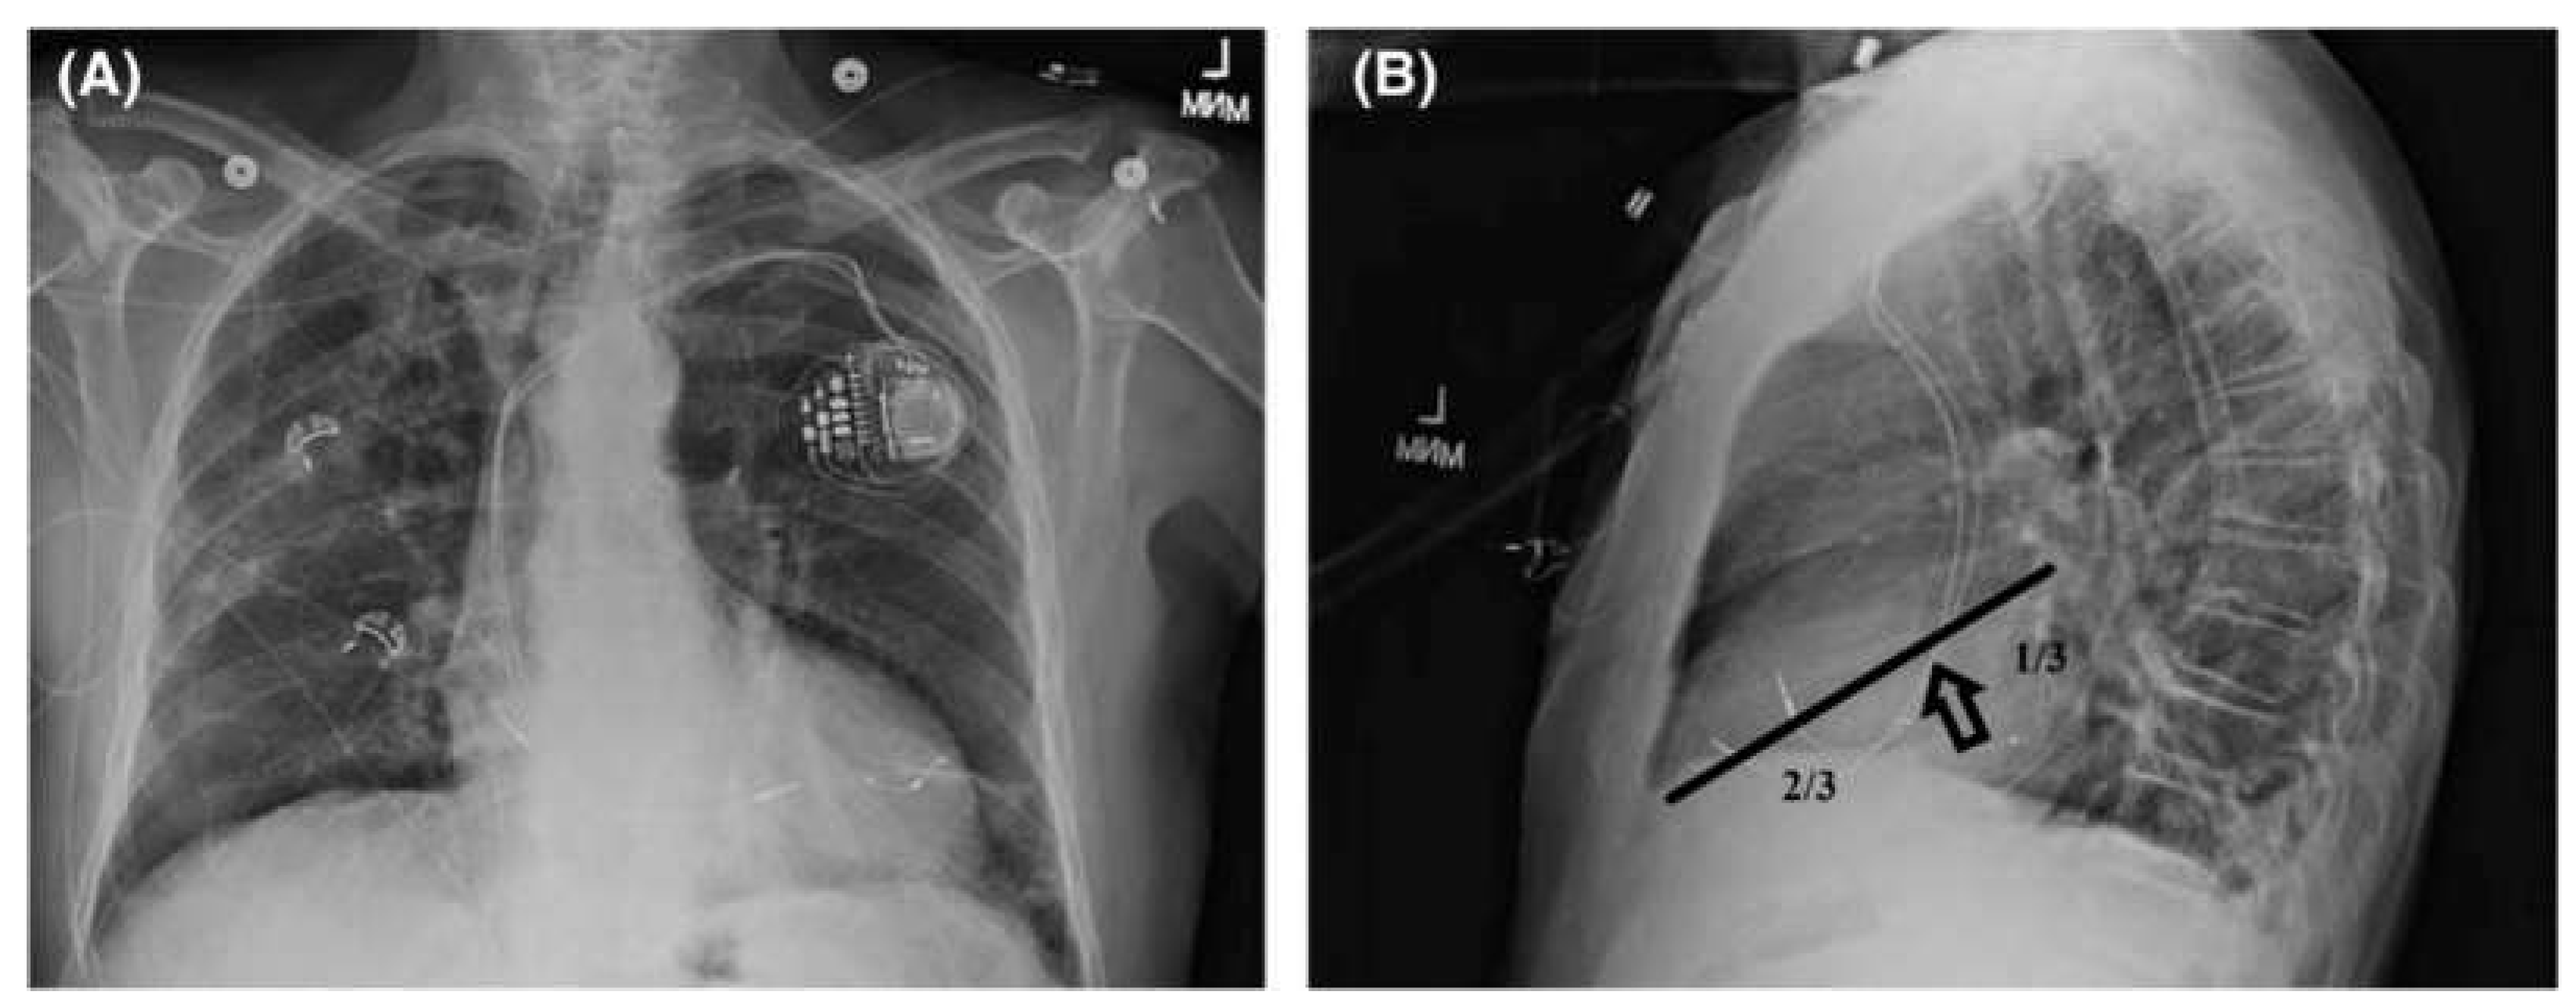

Chest X-Ray Posterior Anterior and Lateral (determine ideal lead positions)

Examine lateral chest X-ray determining which of the 4 lead positions are optimal (20 possible choices). To optimize longitudinal dyssynchrony choose the best lead configuration - 1/3 distance from the base or 2/3 distance from the apex.

Figure 1.